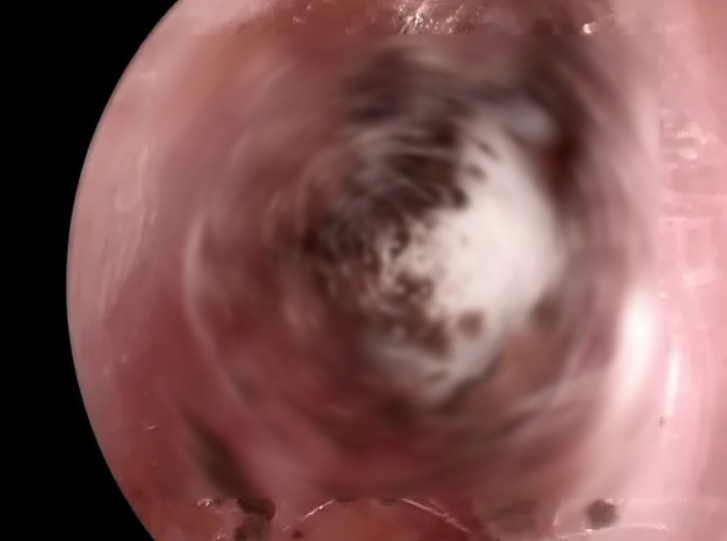

耳道内长满了白色绒毛状真菌丝团。

接诊医生蔡洁询问后得知,王先生的耳朵痒了快一个月,时有胀痛,耳内仿佛被堵上了一团棉花,听力也跟着下降。她用耳内窥镜仔细检查了王先生的耳道,耳道内长满了白色绒毛状真菌丝团,就像发霉一样。